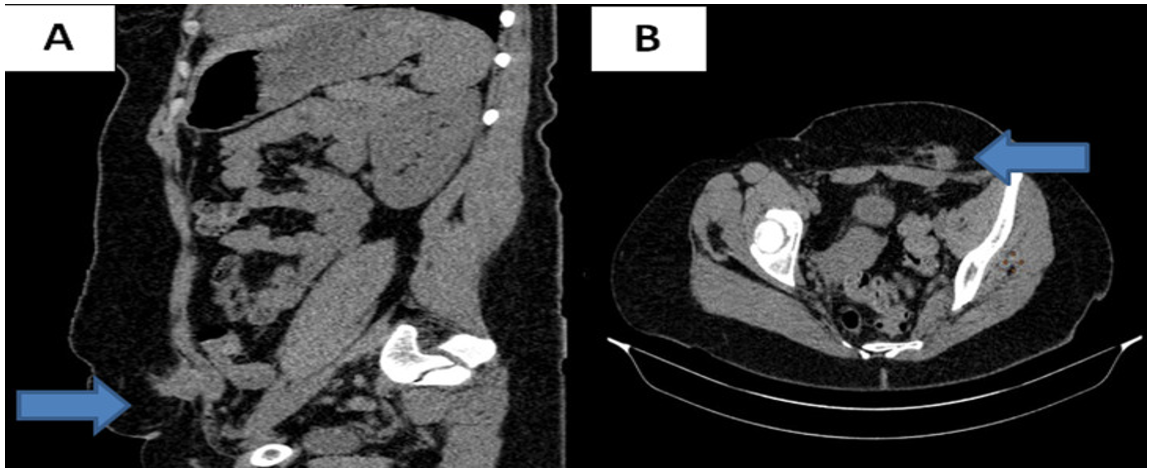

Diagnostic approach: abdominal CT scan found two nodules of 3x2 cm and 1x2 cm in the rectus muscles on either side of the Pfannenstiel scar, of the same density before and after injection of contrast medium as the uterus, suggesting endometriosis lesions. Pelvic MRI was performed to better identify the lesions and to look for deep pelvic endometriosis lesions warranting possible medical treatment. Pelvic MRI showed multiple endometriotic nodules over the entire caesarean section scar, including one measuring 17x19 mm embedded in the subcutaneous fat and in the thickness of the right and left rectus muscles (Figure 2). In addition, there were no lesions in favour of deep pelvic endometriosis.

Figure 2: Coronal section of a T1-weighted pelvic MRI fat saturation sequence (FATSAT); left paramedian nodule located on the caesarean scar measuring 17x19 mm